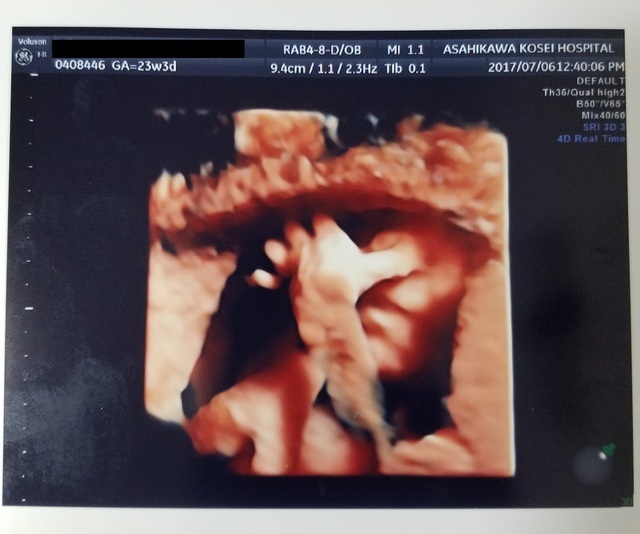

23週3日(23w3d・男の子)|きどあさ さん(28歳)

エコー写真撮影時のエピソード:

胎盤で目元は隠れてるけど鼻をいじっているところを見れました。お腹の中でもたくさん動いていろんなことをしているんだな~と感動しました。

鼻を触ってる姿だったけど、母はよっ‼ってやってるようにも見えるねって話してました。